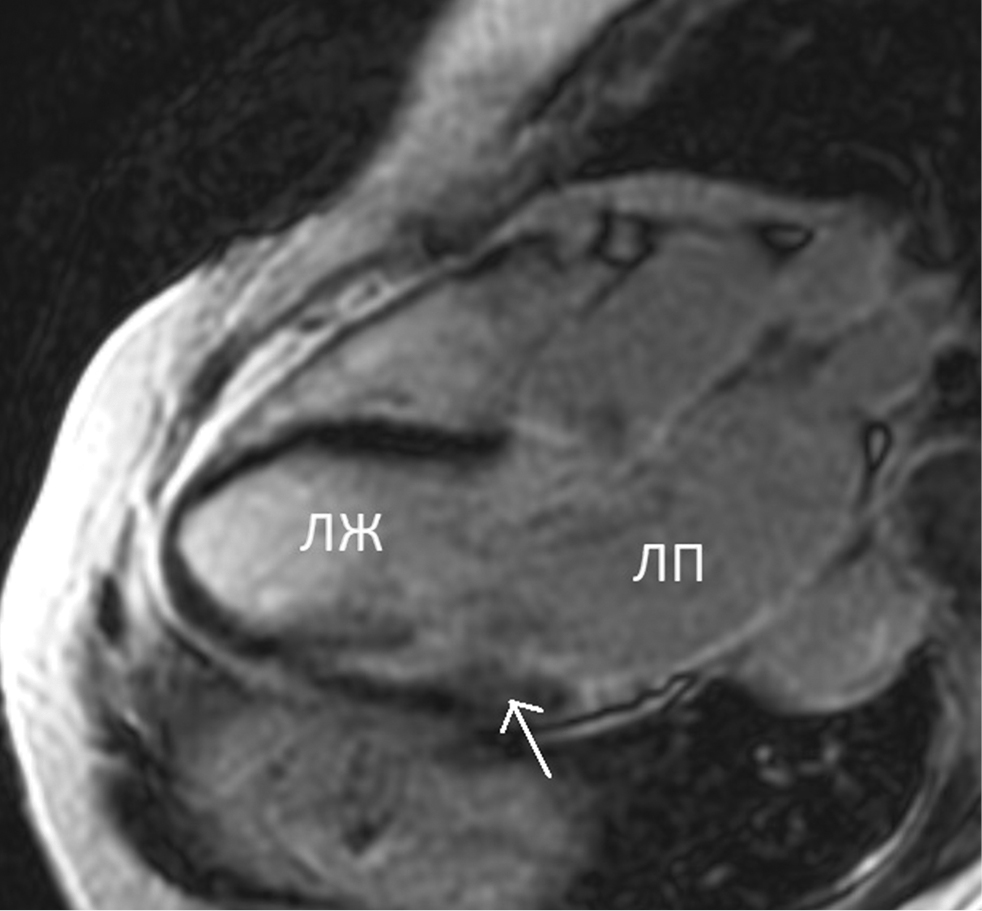

After intravenous CA administration in the delayed phase (myocardial delayed enhancement), an extended area of intramural accumulation of a nonischemic CA was identified and localized in the lower and posterolateral segments (4, 5) of the left ventricular basal sections (Figs. 4 and 5). No focal accumulation of CA was noted in areas with increased T1 relaxation time.

Fig. 5. Cardiac MRI. Three-chamber view. Late gadolinium enhancement. The arrow indicates a low-intensity intramural zone of contrast accumulation at the level of 5th segment left ventricle. ЛЖ — left ventricle; ЛП — left atrium

Рис. 5. Магнитно-резонансная томография сердца. Трехкамерный вид. Отсроченное контрастирование. Стрелкой указан слабоинтенсивный интрамуральный участок накопления контрастного вещества на уровне 5-го сегмента левого желудочка. ЛЖ — левый желудочек; ЛП — левое предсердие